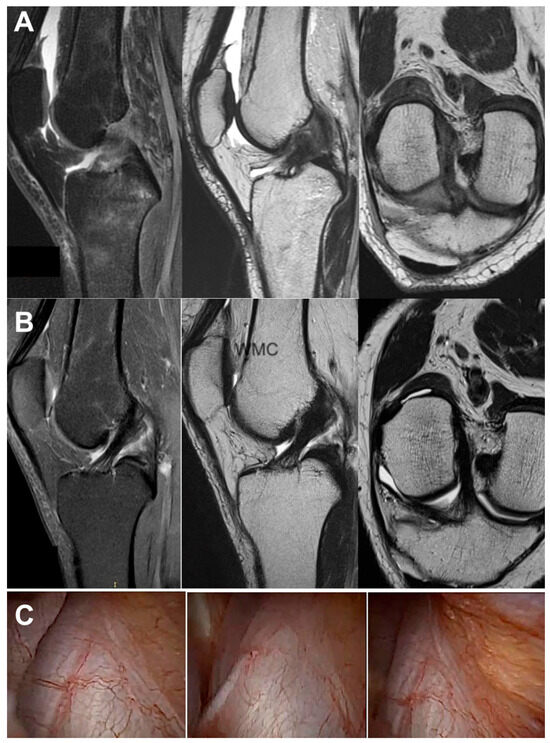

2.4. Imaging Examination

3.3. Imaging Analysis